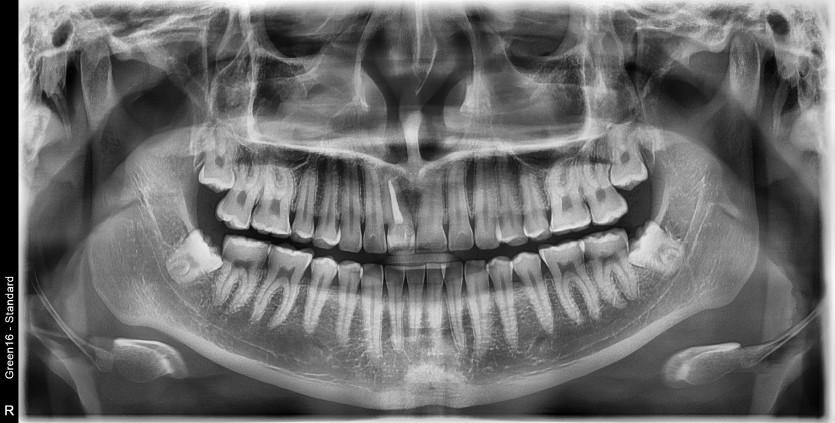

#18,28,38,48 사랑니 발치

구강 외과 전문의가 당일 발치했습니다.